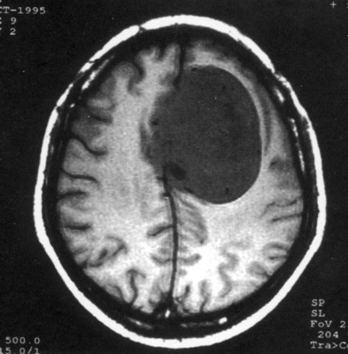

病历摘要:??患者女性,37岁。大便时突起炸裂样头痛3小时,伴喷射样呕吐。既往体健。体检:T37.5℃,BP145/90mmHg,R20次/分,P85次/...

问题 病历摘要:??患者女性,37岁。大便时突起炸裂样头痛3小时,伴喷射样呕吐。既往体健。体检:T37.5℃,BP145/90mmHg,R20次/分,P85次/分。神志清楚,颅神经检查无异常,颈强直,克、布氏征(-),四肢肌力、肌张力正常,病理征(-)。 为明确诊断,可考虑作什么检查?